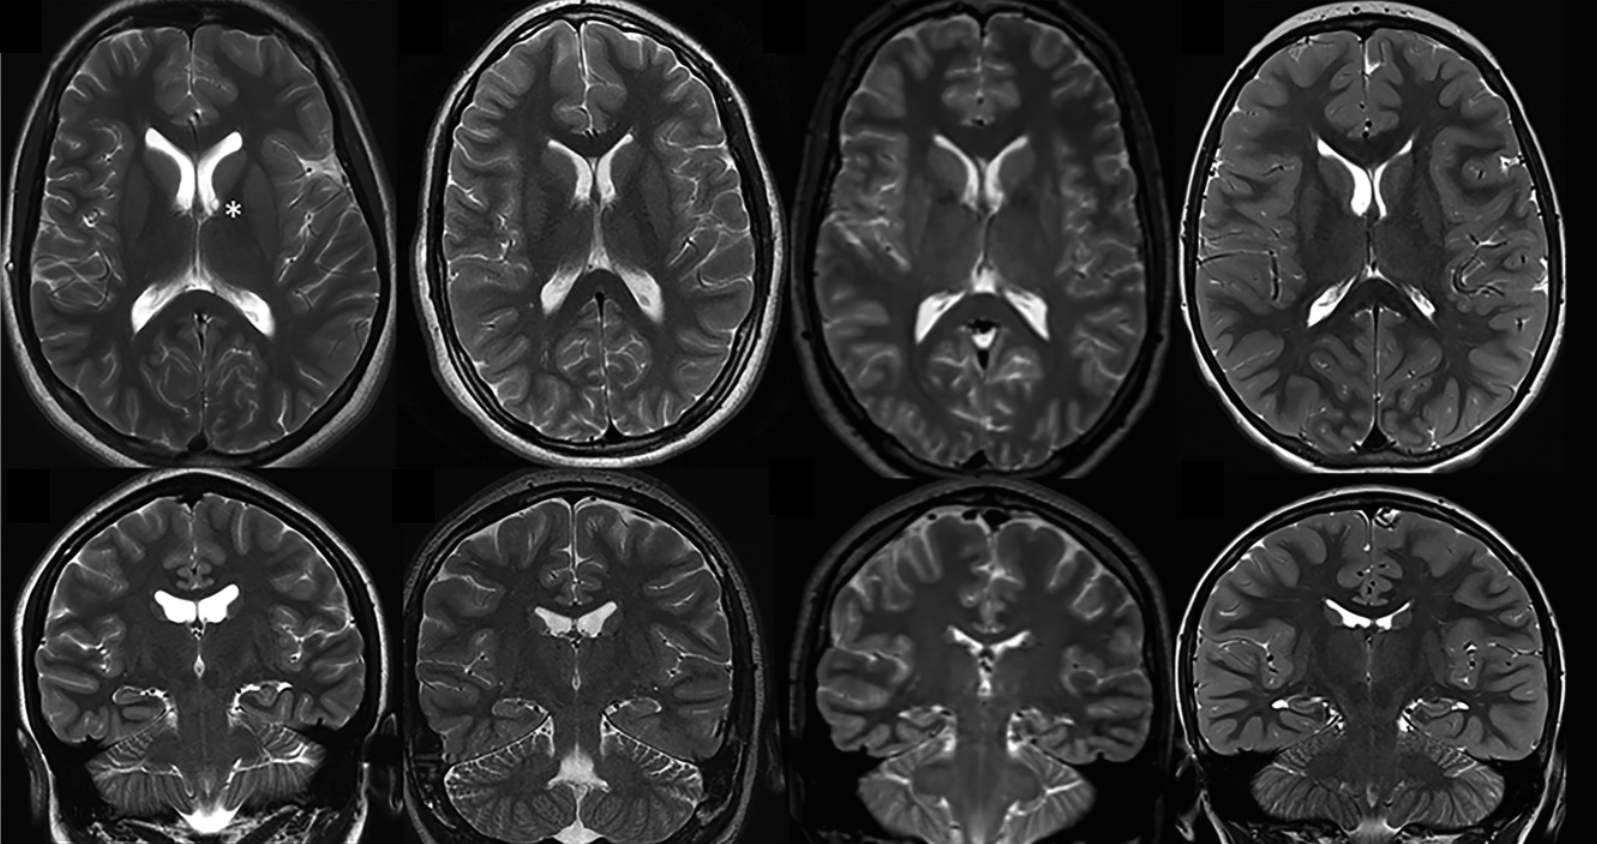

Mosaic of Brain MRI Stock Image C012/3798 Science Photo Library Mosaic Brain Definition the mosaic brain evolution hypothesis, stating that brain regions can evolve relatively independently during. somatic mosaicism refers to the fact that cells within an organism have different. the hypothesis of mosaic brain evolution relies on the selective forces acting on specific areas of the brain, whose. brain mosaicism has diverse origins, from early embryogenesis to neurogenesis. Mosaic Brain Definition.

Mosaic of Brain MRI Stock Image C012/3799 Science Photo Library Mosaic Brain Definition The useful technique of single cell sequencing has been instrumental in recent discoveries about neuronal genetic diversity. mosaic cognition refers to the fact that the mammalian brain is composed of various functionally separate. genomic mosaicism describes the phenomenon where some but not all cells within a tissue harbor unique genetic mutations. somatic mosaicism refers to the fact. Mosaic Brain Definition.

Mosaic of Brain MRI Stock Image C012/3800 Science Photo Library Mosaic Brain Definition brain mosaicism has diverse origins, from early embryogenesis to neurogenesis and in the mature brain. somatic mosaicism refers to the fact that cells within an organism have different. we now know that the mosaic brain is even more genetically diverse than previously thought, and this may have fascinating implications for human individuality. The useful technique of single. Mosaic Brain Definition.